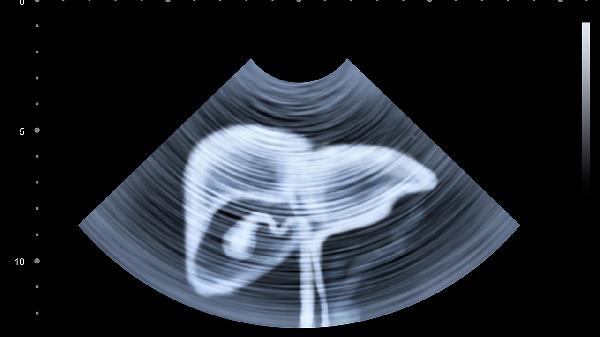

肝脏疾病患者除药物治疗外,需保持低脂高蛋白饮食,适量摄入新鲜蔬菜水果补充维生素。避免熬夜和过度劳累,严格禁酒并控制体重,慎用对肝脏有损伤的药物。建议每3-6个月复查肝功能、超声等检查,出现皮肤黄染或腹胀等症状应及时复诊调整治疗方案。